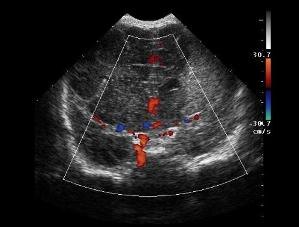

‼️Когда вы делаете УЗИ — требуйте ДОПЛЕР. Это не роскошь. Это необходимость. Я раньше наивно думала, что это делают всегда. Ну как иначе? Это же УЗИ, полноценное обследование. Но реальность другая: не все врачи включают доплер. Даже когда это жизненно важно. А теперь внимание: если вы проходите обследование с онкологической настороженностью — доплер должен быть обязательно. ✅ Опухоли любят кровоснабжение. Они «тянут» к себе сосуды. ✅ Доплер показывает, как течёт кровь в новообразовании. И если сосуды хаотичные, усиленные, атипичные — это сигнал. Иногда — очень тревожный. ✅ Можно отличить доброкачественное от злокачественного. Киста? Нет кровотока. Опухоль? Есть, и какой! ✅ Видно, есть ли метастазы — по изменённым лимфоузлам. ✅ Можно отслеживать динамику — работает ли лечение. 🚫 Без доплера — это просто картинка. 🚫 Без доплера можно пропустить рак. Да, так и есть. Что иногда пациент должен спрашивать сам: «А вы доплер включаете? Это с доплером?» А должен ли он вообще это контролирова

✅ Доплер показывает, как течёт кровь в новообразовании. И если сосуды хаотичные, усиленные, атипичные — это сигнал. Иногда — очень тревожный.

✅ Можно отличить доброкачественное от злокачественного. Киста? Нет кровотока. Опухоль? Есть, и какой!